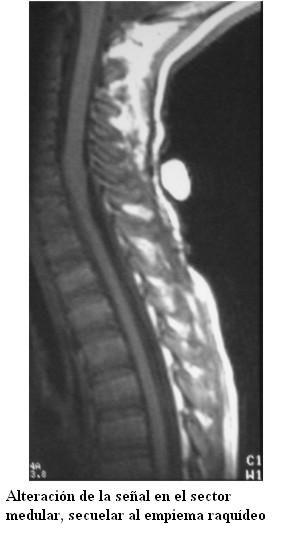

En los controles posteriores se observa mejoría de la sintomatología neurológica, pero se destaca que luego de un año del inicio de la enfermedad el niño persiste con síntomas de liberación piramidal sin afectación funcional. La resonancia magnética de control a los 3 meses del diagnóstico muestra mejoría de la colección intrarraquídea, con persistencia de discreta alteración medular (figura 3).